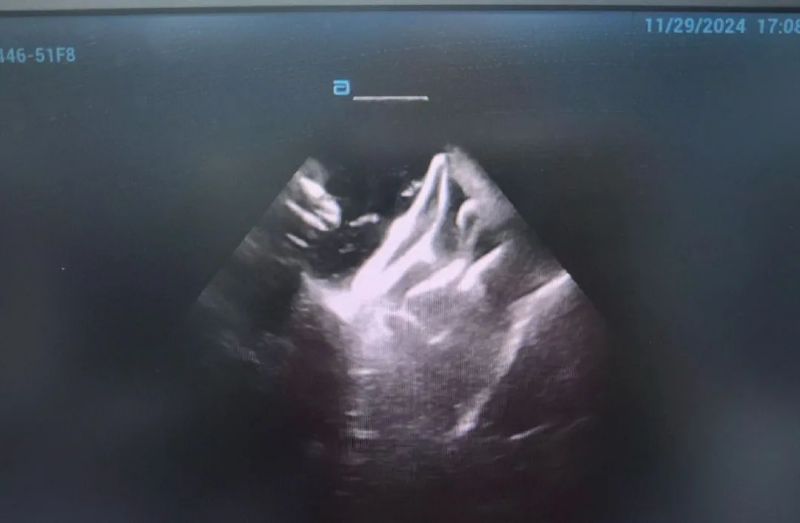

此次手術患者均為持續性房顫患者,由延安大學咸陽醫院吳棟梁院長、心律失常專家劉雄濤副院長帶領介入團隊開展,安全高效、圓滿完成手術,手術過程患者全程清醒,術中自訴感覺良好,無痛苦感受。術后患者的心律恢復并維持了竇律,目前恢復情況良好,無任何并發癥出現。